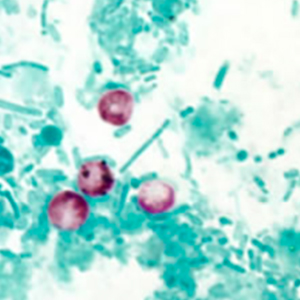

Les oocystes de cryptosporidie ne se colorent pas au Lugol. Ce sont des petites structures rondes mesurant entre 4 et 6 μm de diamètre, réfringentes. Leur contenu n’est pas visualisable en microscopie optique. Leur identification nécessite une coloration de Ziehl-Neelsen modifiée ; ils sont alors colorés en rose-rouge sur un fond bleu-vert. Il n’est pas possible de distinguer les différentes espèces sans technique de biologie moléculaire (Hoffman, 2017).